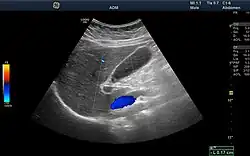

Ultrasound image showing the liver, gallbladder and common bile duct.

Medical ultrasound uses high frequency broadband sound waves in the megahertz range that are reflected by tissue to varying degrees to produce (up to 3D) images. This is commonly associated with imaging the fetus in pregnant women. Uses of ultrasound are much broader, however. Other important uses include imaging the abdominal organs, heart, breast, muscles, tendons, arteries and veins. While it may provide less anatomical detail than techniques such as CT or MRI, it has several advantages which make it ideal in numerous situations, in particular that it studies the function of moving structures in real-time, emits no ionizing radiation, and contains speckle that can be used in elastography. Ultrasound is also used as a popular research tool for capturing raw data, that can be made available through an ultrasound research interface, for the purpose of tissue characterization and implementation of new image processing techniques. The concepts of ultrasound differ from other medical imaging modalities in the fact that it is operated by the transmission and receipt of sound waves. The high frequency sound waves are sent into the tissue and depending on the composition of the different tissues; the signal will be attenuated and returned at separate intervals. A path of reflected sound waves in a multilayered structure can be defined by an input acoustic impedance (ultrasound sound wave) and the Reflection and transmission coefficients of the relative structures.[20] It is very safe to use and does not appear to cause any adverse effects. It is also relatively inexpensive and quick to perform. Ultrasound scanners can be taken to critically ill patients in intensive care units, avoiding the danger caused while moving the patient to the radiology department. The real-time moving image obtained can be used to guide drainage and biopsy procedures. Doppler capabilities on modern scanners allow the blood flow in arteries and veins to be assessed.